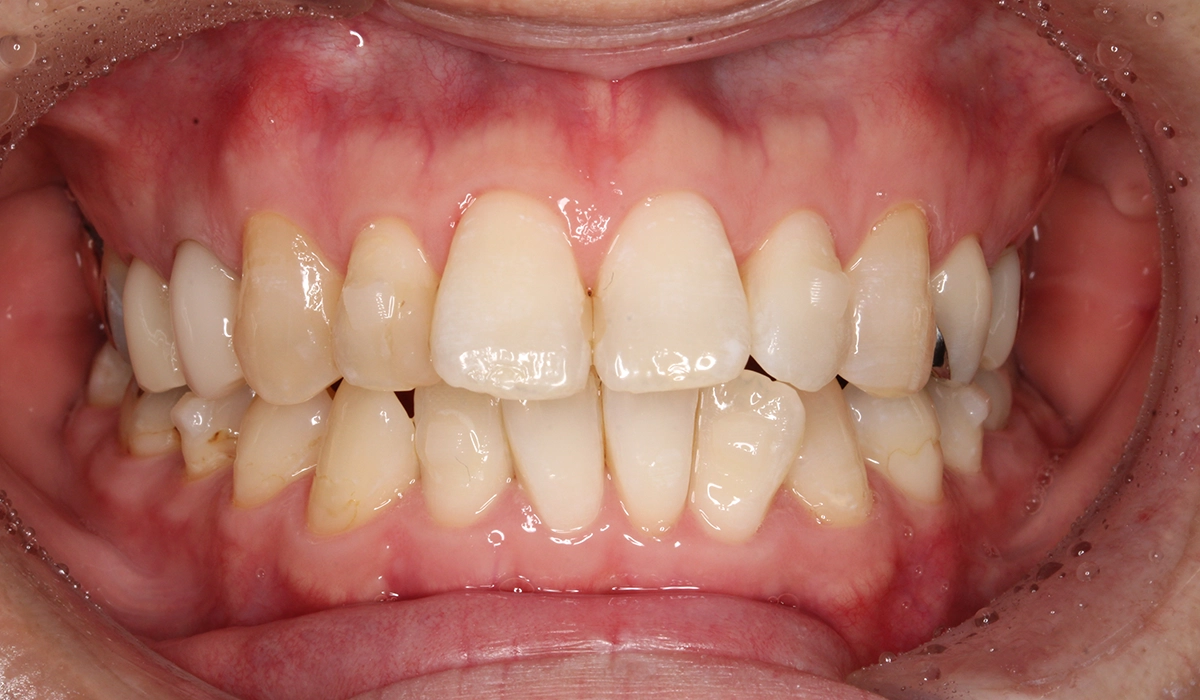

術前:正面

術後:正面